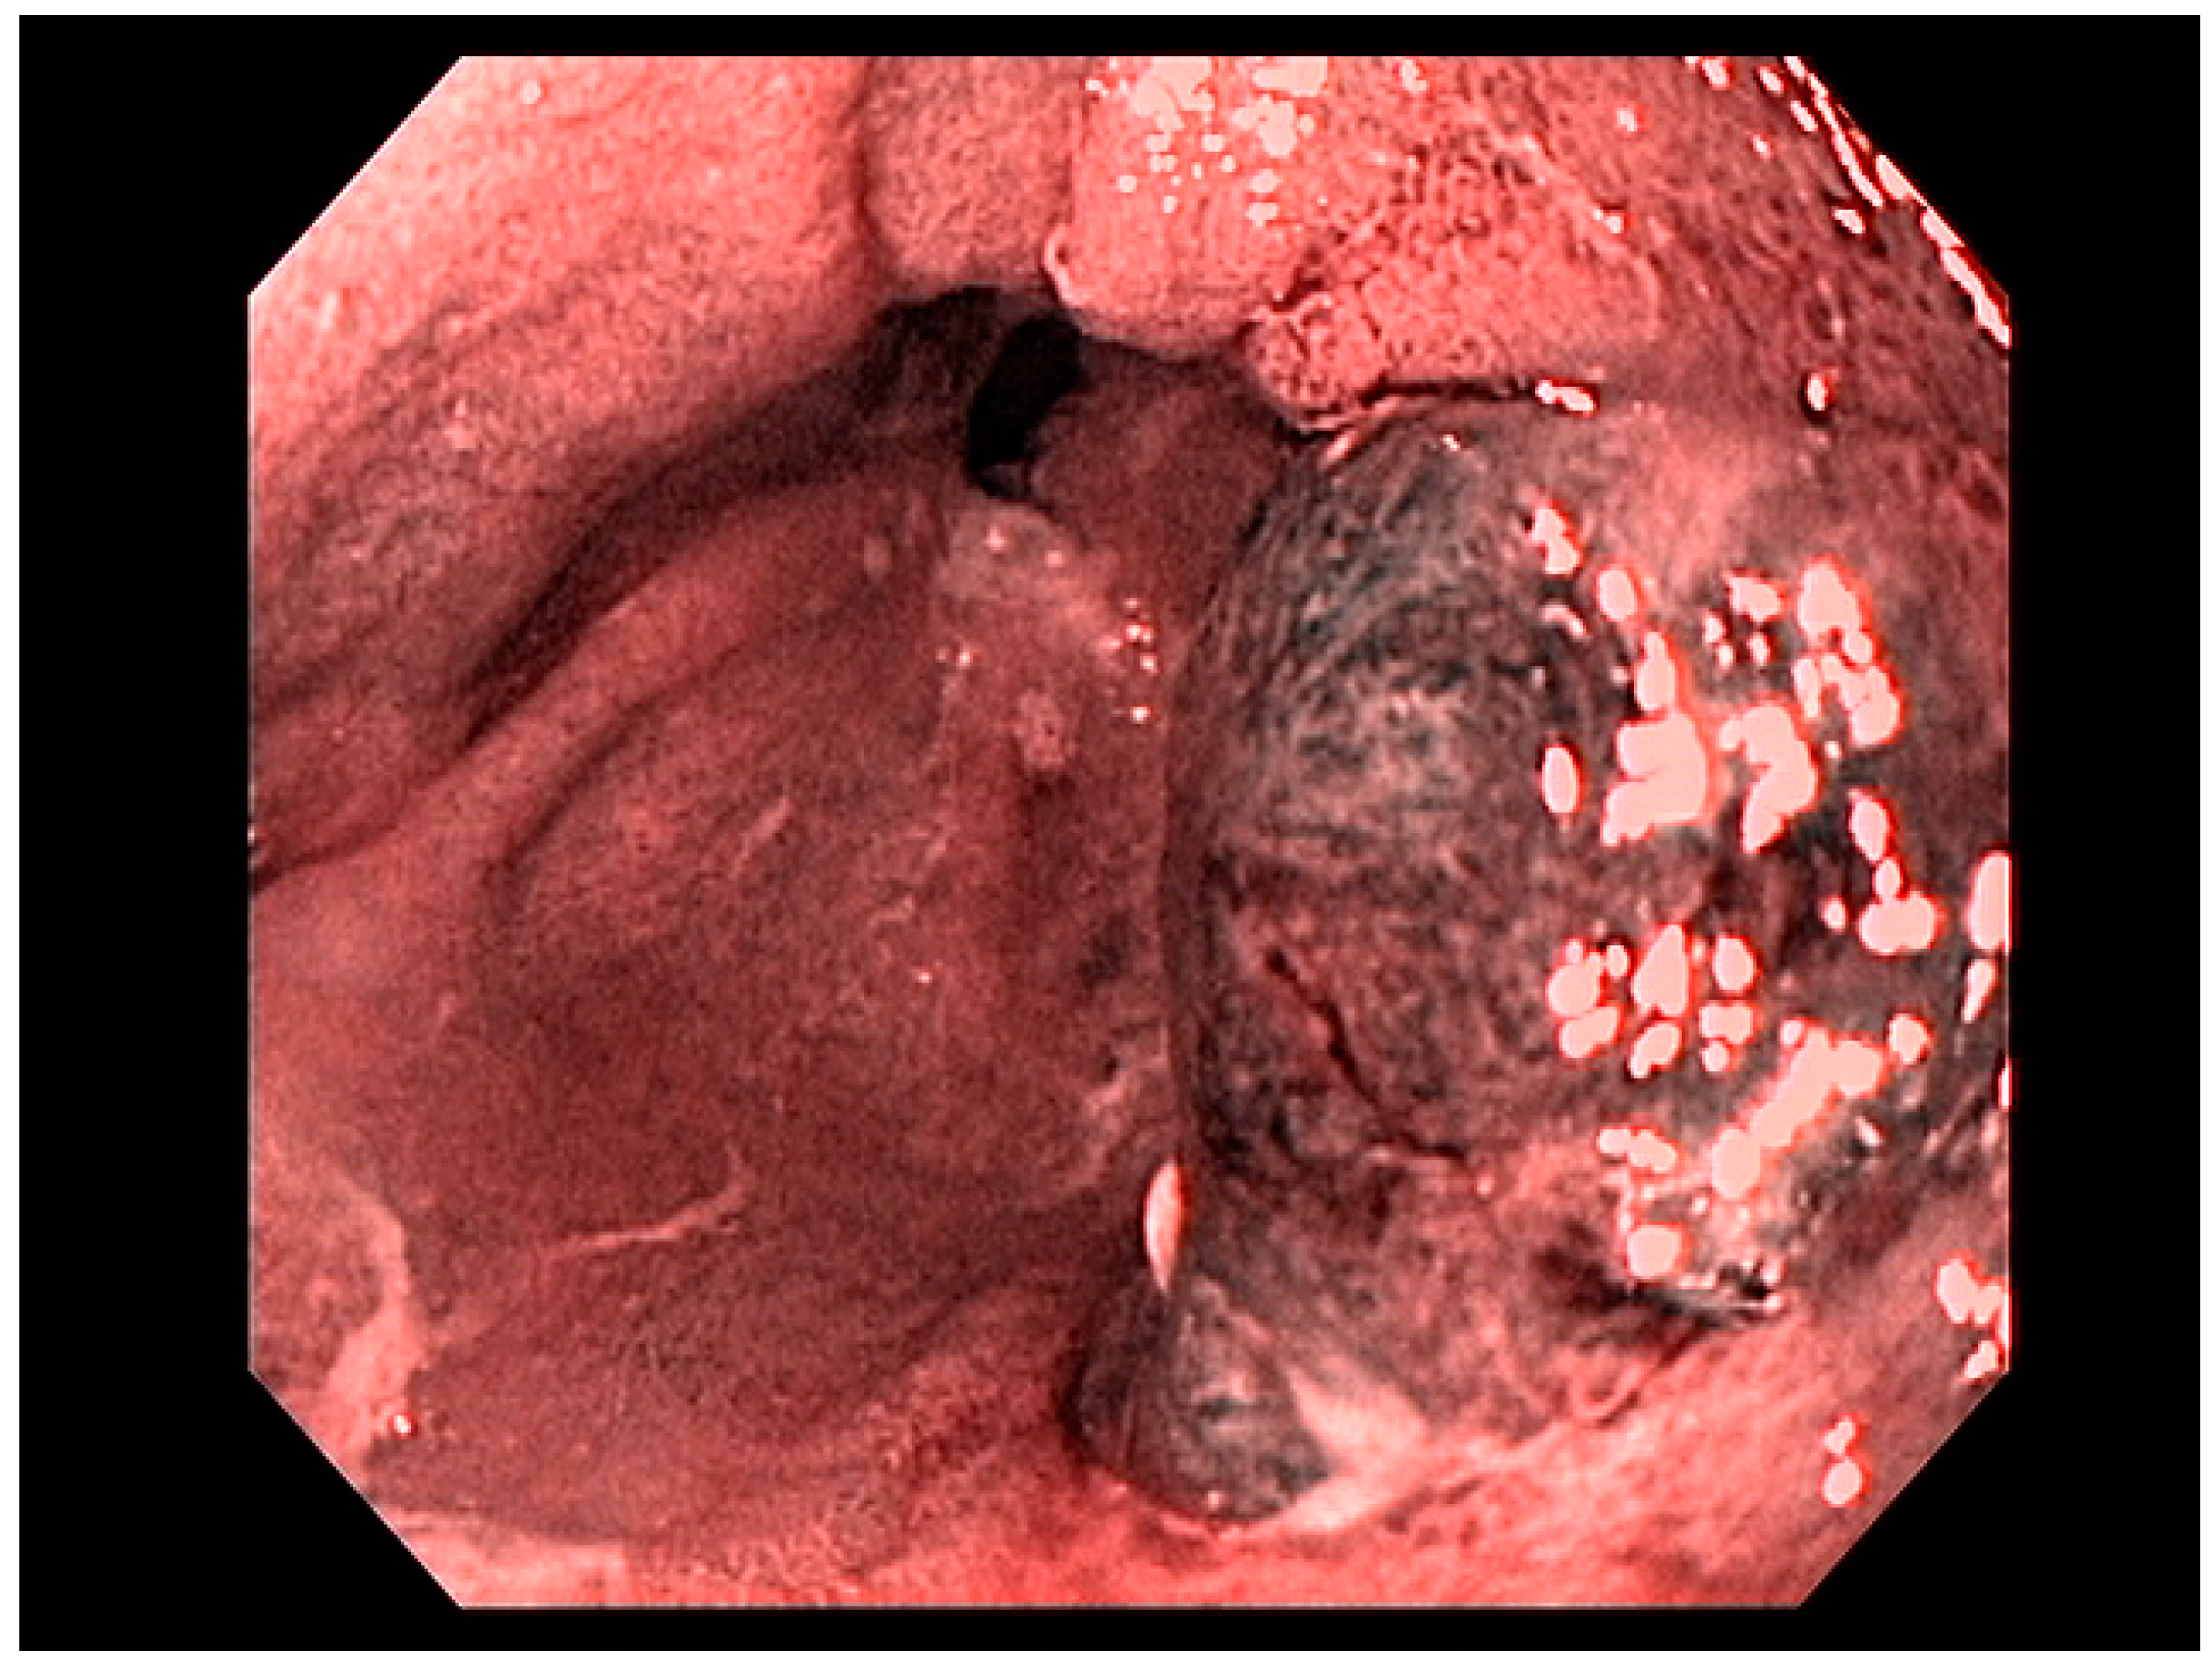

4. Gastric Malignancies

4.1. Gastric Adenocarcinoma

4.2. Early Gastric Cancer (EGC)

4.3. Endoscopic Ultrasound in Staging of Gastric Cancer

4.8. Treatment